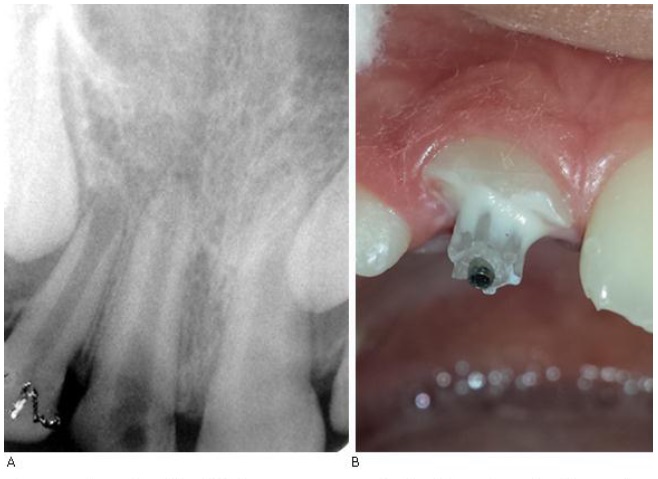

Según datos aportados por el paciente y sus padres, el accidente ocurrió cuando el niño se impactó contra el borde de una acera, mientras jugaba. Resultó ser una fractura complicada de corona en 11, sin sangrado periodontal (el paciente y sus familiares no aportan el fragmento fracturado). De inmediato acuden al servicio de estomatología más cercano, donde se practicó inicio de tratamiento endodóntico de urgencia estándar. Mediante rayos X, se pudo constatar que el paciente no presentaba otra complicación endoperiodontal y que el estado de formación apical era incompleto, coincidente con un Kuttler IV (Fig. 1a). Se le aplicó anestesia local, se procedió a realizar la extirpación pulpar total del diente afectado, se colocó medicamento intraconducto de Dentofar® y se realizó restauración temporal con cemento de policarboxilato de zinc. Además se indicó reposo masticatorio. Fue remitido a su área de atención y se adjuntó una radiografía periapical inicial.

A) Radiografía inicial. Muestra presencia de formación apical incompleta con un Kuttler IV. B) Cementación de la cánula con ionómero de vidrio.

12. Cementación de cánula rígida No. 22, con ionómero de vidrio tipo II (Fig. 1b).